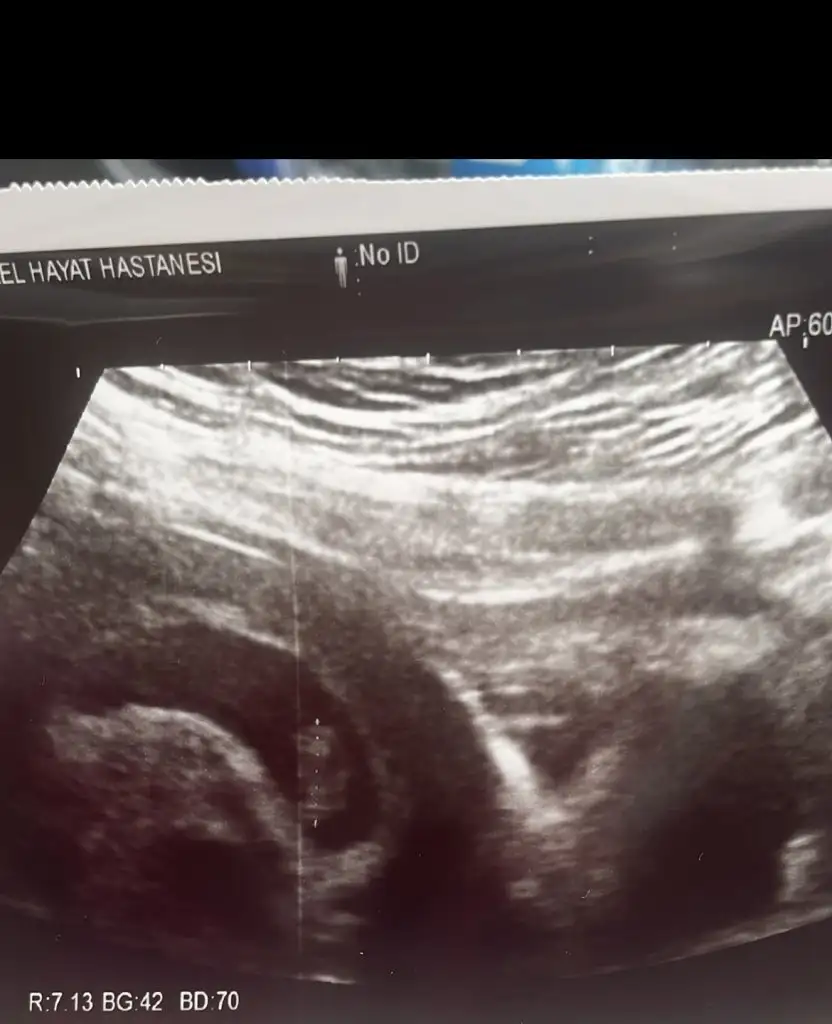

Bi ara atim sana usg fotoğrafini simdi fitil attım kalkmam imkansizMantığını baya çözdüm gibi :) 6.haftalardaki usg görüntüsünde bebek kesenin sağındaysa kız, soyundaysa erkek diyo Ramzitabi bu karından ultrasona göre. Vajinalse tam tersi oluyomuş

Sanki kesenin solunda gibi görünüyo, Ramziye göre erkek oluyo bu durumda ama vajinal bakılmış o zaman tersi olur, yani kız olabilir bu bebiş

Seninde kız gibi duruyor canım sağlıkla gelsin inşAllahHahah bunu ilk defa duyuyorum ya bana da bir yorum yapalım mıay fala döndürdük iyice mevzuyu ultrason karından